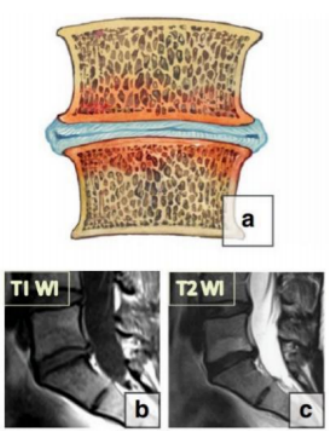

目前最常用的 Modic 改变分型是 1988 年 Modic 等提出的经典分型:

Ⅰ 型代表急性炎症和水肿改变,在 T1WI 呈低信号而 T2WI 呈高信号;

Ⅱ 型代表骨髓的脂肪变性, 在 T1WI、 T2WI 均呈高信号;

Ⅲ 型代表终板下骨硬化,在 T1WI、 T2WI 均呈低信号。